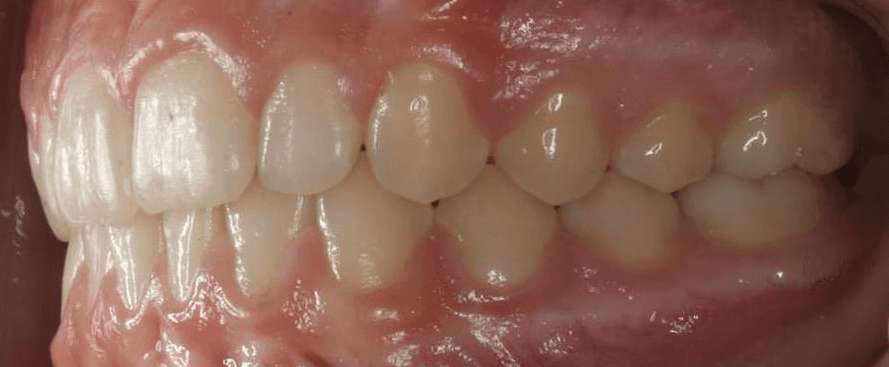

Final results

INTRAORAL